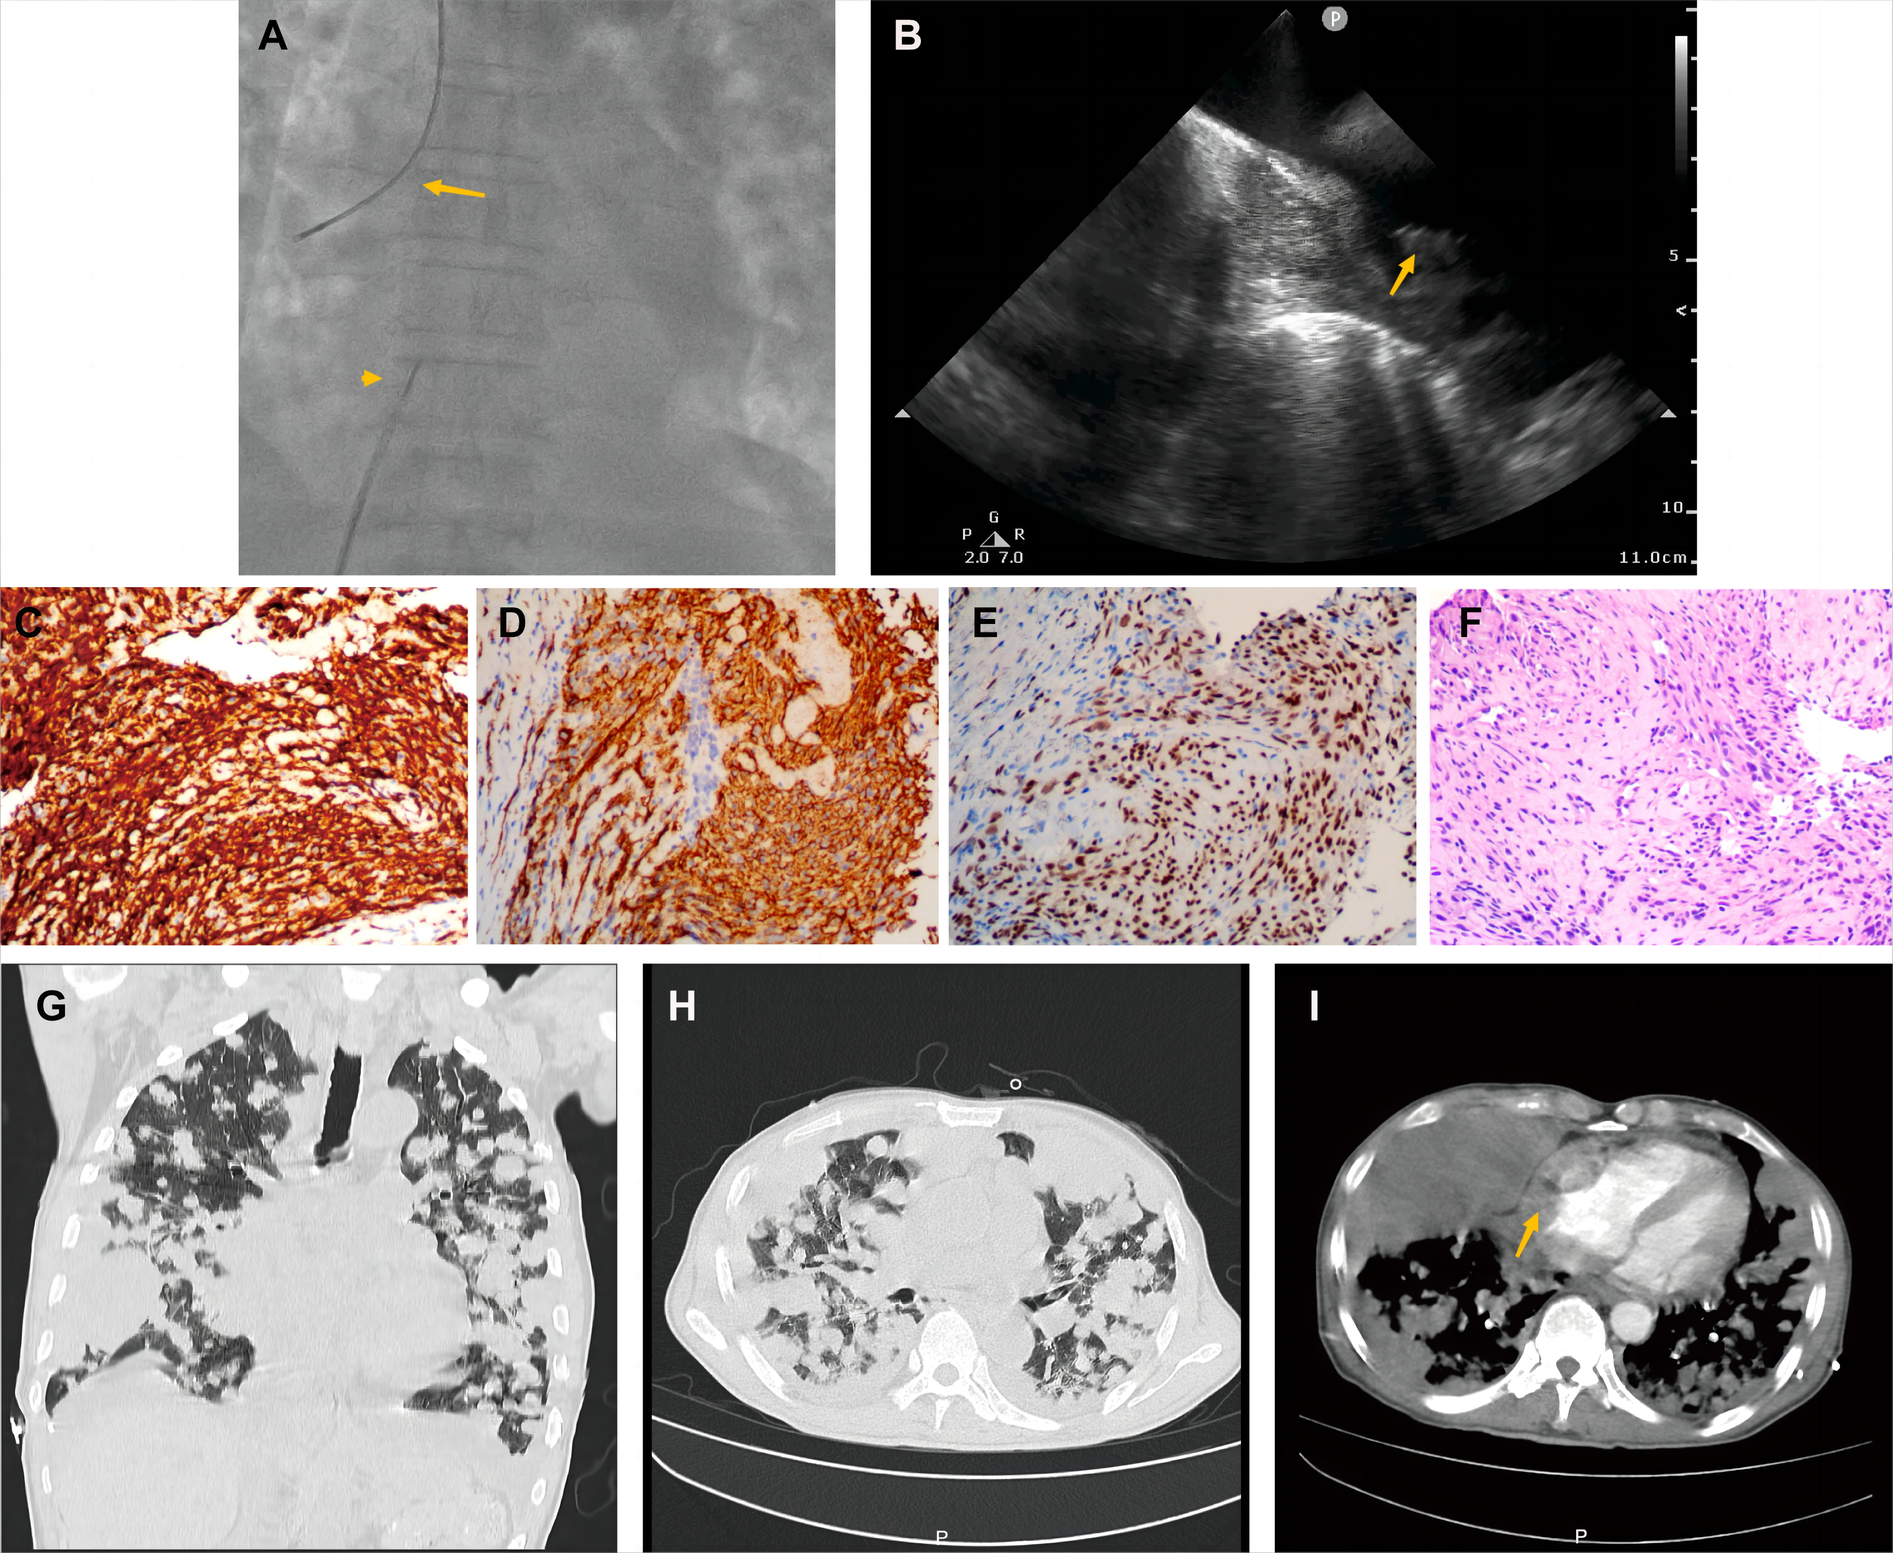

A 70-year-old man presented with progressive dyspnea and weakness for one month. His physical examination, including the cardiovascular examination, was unremarkable. He had low-grade pyrexia of 37.8°C, with no cough and sputum. Oxygen saturations were 97% on room air. Blood tests showed normocytic anemia (90 g/L), elevated C-reactive protein (CRP) (33.4 mg/L), leucocyte count (12.7 × 109/L), pro-Brain natriuretic peptide level 406 pg/ml, D-dimer of 9840 ug/L, and tumor marker CA125 (312.1 U/ml). Chest X-ray (Figure 1A) and computed tomography (Figures 1B,C) revealed striking extensive pulmonary lesions, a large soft tissue mass in the right atrium (RA), and pleural effusion. He had persistent bilateral bloody pleural fluid. Thoracentesis removed bloody exudative fluid without malignant cells. Superficial lymph nodes ultrasonography revealed left subclavian lymphadenopathy. Pathological results of lung biopsy and lymph nodes were nondiagnostic. Contrast-enhanced CT showed a hypodense oval filling contrast defect at the right atrium (RA) (Figure 1D) 18F-fluorodeoxyglucose positron emission tomography/CT revealed focal uptake in the RA mass (with SUVmax of 5.8), and scattered uptake in lung and pleura metastatic (Figure 1E). Echocardiogram showed a large mass (22 × 41 mm) in the RA invading the superior vena cava (Figure 1F). Ultrasonographical guided right atrial biopsy was performed. An 11F sheath containing an intracardiac ultrasonography catheter (Biosense Webster, Johnson & Johnson, USA) was inserted into the right atrium through the right femoral vein while under local anesthesia with 1% lidocaine. By crossing the tricuspid annulus, the mass' size and extent could be clearly seen. Under the guidance of ICE, a cardiac biopsy forceps (Argon, USA) was inserted into the right atrium via the right internal jugular vein and clamped atrial tissue. The RA mass was visualized and five biopsies were performed (Figure 2A,B, Supplementary Appendix Video S1-2). Of those samples, 3 were mixtures of necrotic myocardium, and 2 were diagnostic for EHE. Histopathology results (Figures 2C–F) revealed a spindle cell tumor, staining with CD34, CD31, and ERG expression, confirming the diagnosis of cardiac epithelioid hemangioendothelioma (EHE). A multidisciplinary team (oncologists, cardiologists, and respiratory doctors) evaluated this patient and recommended chemotherapy and targeted therapy with no mass resection. Unfortunately, the patient's condition deteriorated quickly due to aggressive pulmonary lesions (Figures 2G–I), and he had severe dyspnea. The patient made the decision to receive hospice care.

Figure 1

Chest computed tomography demonstrated cardiac mass of Case1. (A) Chest x-ray and Chest CT images in axial (B) and coronal planes (C) showed remarkable extensive pulmonary lesions. (D) Contrast-enhanced CT showed a hypodense oval filling contrast defect (arrow) at the right atrium (RA). (E) 18F-fluorodeoxyglucose positron emission tomography/CT (18F-FDG PET/CT) showed more uptake in the RA mass (arrow), lung, and pleura. (F) Echocardiography depicted an oval-shaped mass (22 × 41 mm) (arrow) in the RA at the level of the superior vena cava ostium.

Figure 2

Histological endomyocardial biopsy specimen of the right atrium and lung rapid deterioration of Case1. (A) Catheter for intracardiac echocardiography (arrowhead) and cardiac bioptome (arrow). (B) The intracardial echocardiography demonstrates the mass of the right atrium and well-targeted biopsy catheter (arrow) on the mass. (C–F) The representative histologic aspect of the mass. Immunohistochemical staining for CD31(C), CD34 (D), and ERG (E) marker in cytoplasmic. (F) Cells displaying epithelioid morphology, large nuclei, and ample cytoplasm (hematoxylin and eosin). (Original magnification 40X). (G,H) Axial and coronal contrast-enhanced CT scans showed rapid progression of lung metastases, and (I) recurrent bloody pleural effusion one month after hospitalization. The arrow indicates progressive RA mass.